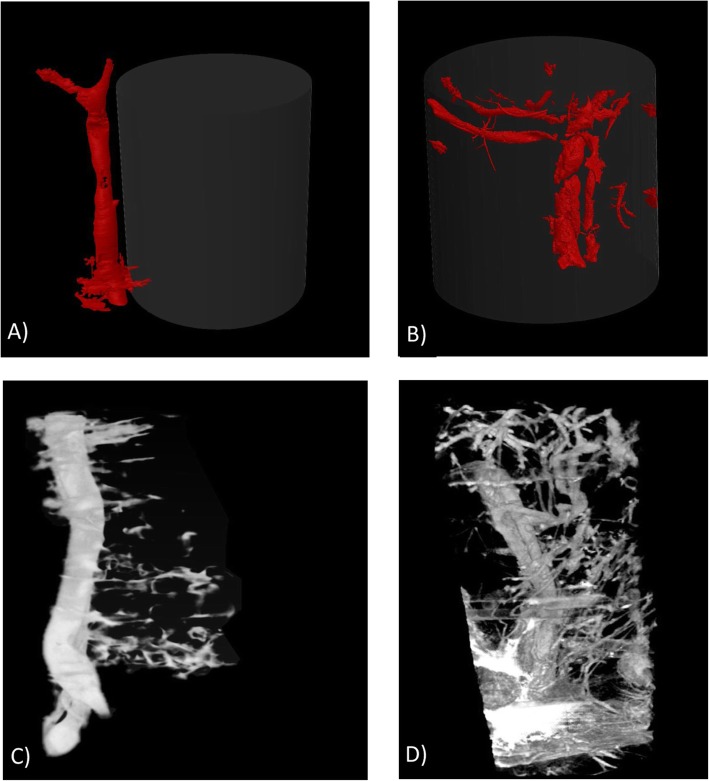

Exploratory μCT imaging of the scaffold vascularity

μCT imaging of samples harvested post-mortem revealed that the vessels created during flow-through prefabrication were fully functional. The presence of contrast agents inside the small vessels revealed the perfusion of the vessels sprouting from the main vascular pedicle (Fig. 6b). Moreover, in vivo analysis showed a dense vascular network sprouting from the main vascular pedicle. Additionally, new vessel ingrowth was observed in the scaffold structure and connected with vessels outside the scaffold (Fig. 6d). In the classic prefabrication group, vessel ingrowth was noted only on the outer surface of the scaffold adjacent to the vascular pedicle (Fig. 6a, c).

Fig. 6.

Scaffold vascularity imaging: The classic (a) and flow-through prefabrication (b) groups were assessed through post-mortem and in vivo μCT imaging (c, d respectively). Small vessels with perfusion that sprouted from the main vascular pedicle were observed in the flow-through prefabrication group (b, d). In the classic prefabrication group, vessel ingrowth was noted only on the outer surface of the scaffold adjacent to the vascular pedicle (a, c)